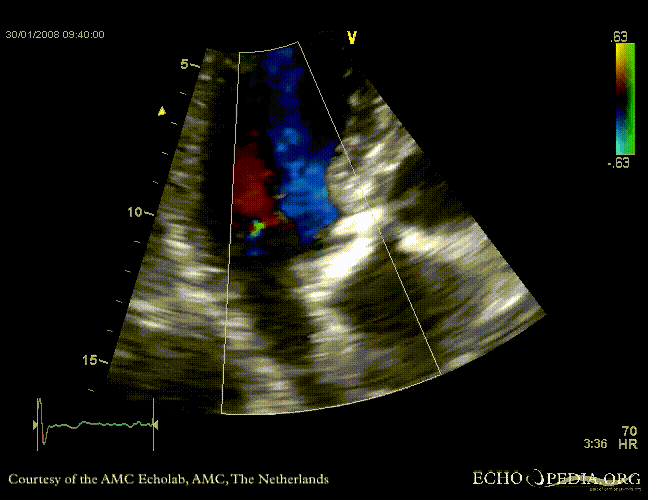

Aortic valve stenosis

AoS9